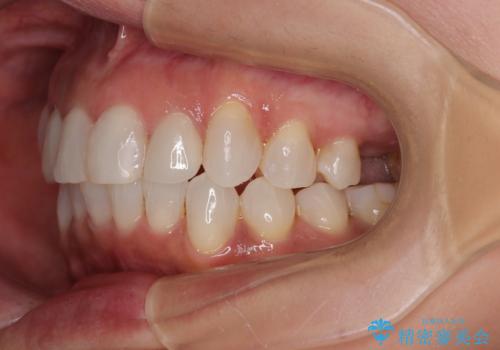

前歯のデコボコとむし歯治療の跡 インビザライン矯正とオールセラミッククラウン治療

- 前歯のセラミッククラウンの縁が見えることが気になってから、デコボコも気になるようになってきたとのことで来院された患者様です。

デコボコの程度は中等度であったため、インビザライン・モデレートパッケージにて歯列を整えることとしました。

セラミッククラウンの装着されていた前歯と、大きな修復治療の跡がある反対側の歯は、矯正治療後に補綴治療を行うこととしました。

奥歯の欠損はインプラント、ブリッジ、入れ歯のどれにすれば良いかを決められず、仕事が非常にお忙しいこともあり、保留としたまま治療を終えることとなりました。

後戻りのリスクがあるため、なるべく早めに欠損補綴治療を開始する予定です。